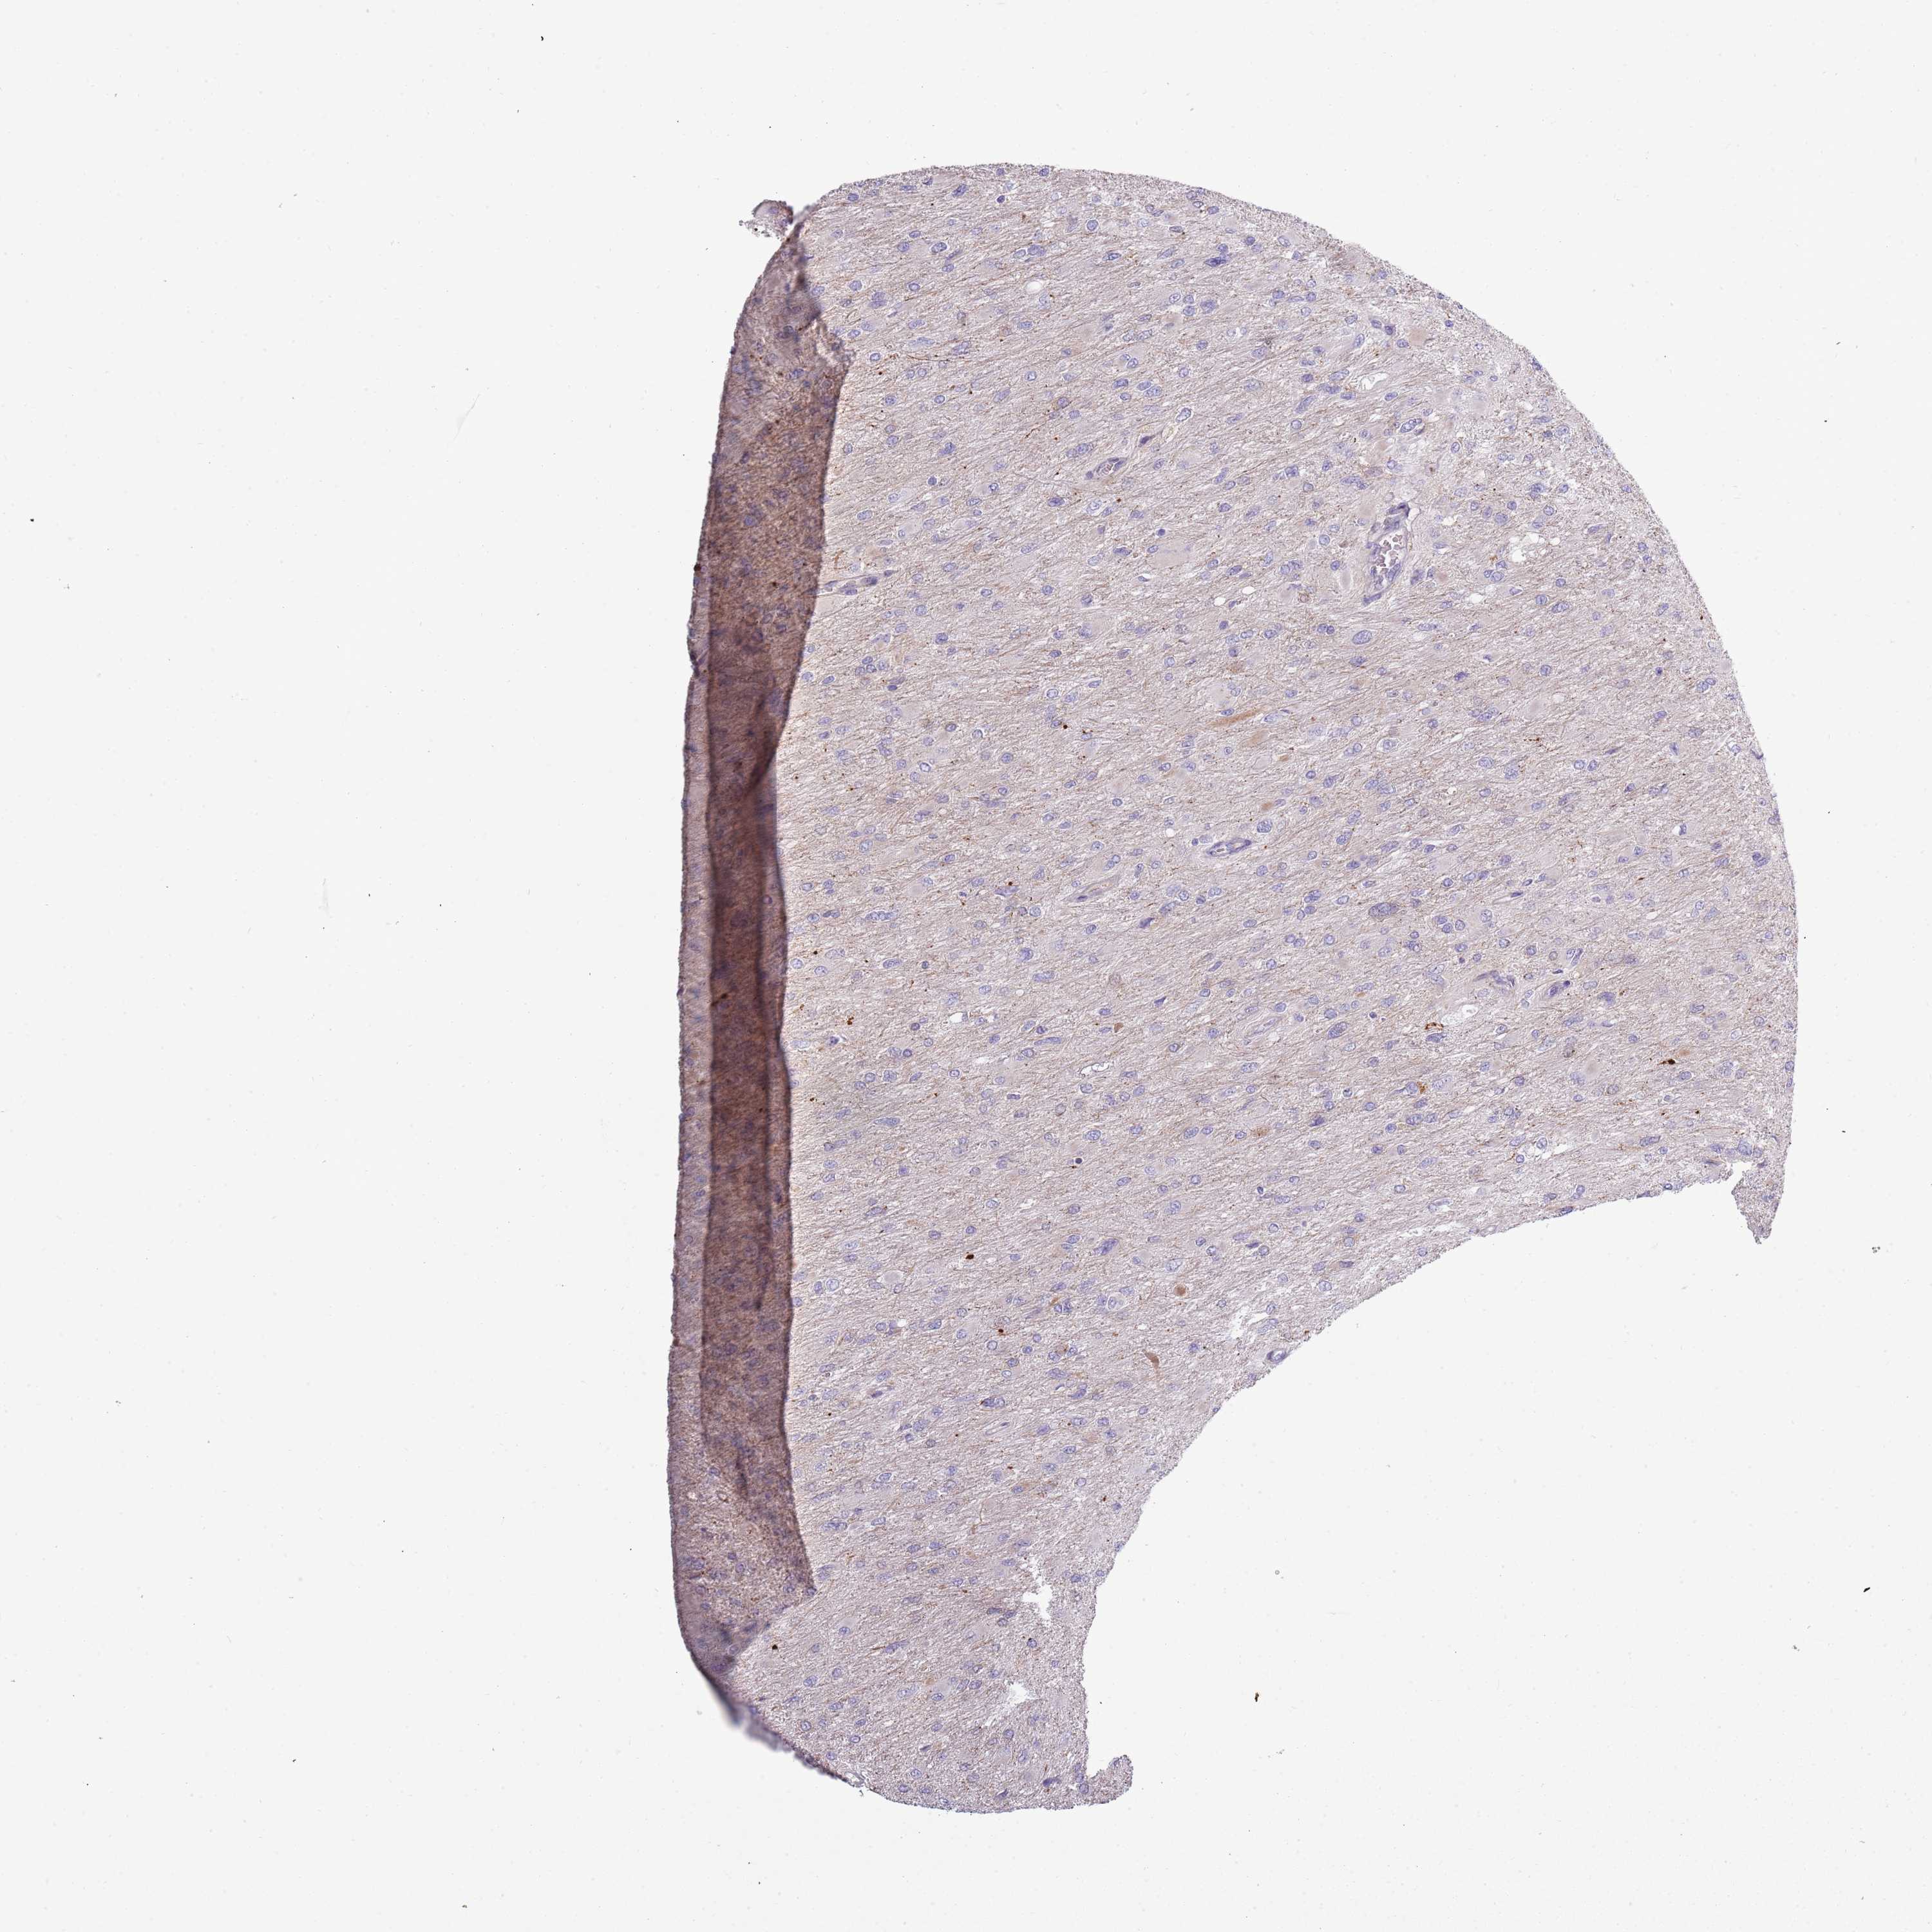

GLIOMA - Protein expressioni

A mouse-over function shows sample information and annotation data. Click on an image to view it in a full screen mode. Samples can be filtered based on level of antibody staining by selecting one or several of the following categories: high, medium, low and not detected. The assay and annotation is described here.

Note that samples used for immunohistochemistry by the Human Protein Atlas do not correspond to samples in the TCGA dataset.

Antibody stainingi

Antibody staining in the annotated cell types in the current human tissue is reported as not detected, low, medium, or high, based on conventional immunohistochemistry profiling in selected tissues. This score is based on the combination of the staining intensity and fraction of stained cells.

Each image is clickable and will lead to virtual microscopy that enables deeper exploration of all samples and also displays staining intensity scores, fraction scores and subcellular localization as well as patient and tissue information for each sample.

Antibody HPA047154

Glioma, malignant, High grade

Glioma, malignant, Low grade